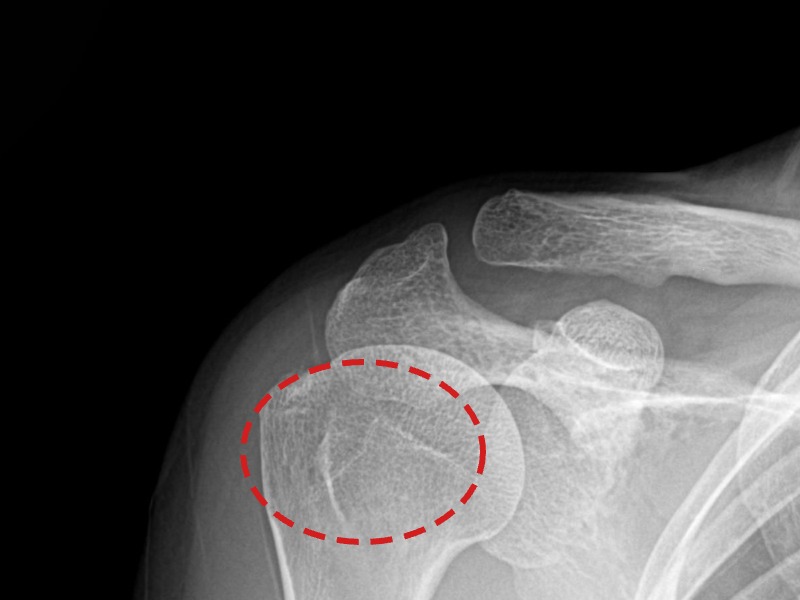

[촬영시기:21.10.21~21.10.30]

[석회분쇄흡입술] 우측 어깨 통증과 운동 제한으로 일상생활이 불편해진 30대 여성 환자로, X-ray에서 우측 극상근건 내 석회 침착이 확인되어 석회분쇄흡입술을 시행하였습니다.